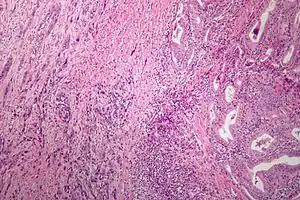

| Microscopic image of anaplastic thyroid carcinoma. H&E stain. | |

Anaplastic tumors have a high mitotic rate and frequently invades the local blood and lymphatic vessels.[5] Cellular death is frequently visualized on microscopic images.[2] The presence of regionally swollen lymph nodes in older patients in whom needle aspiration biopsy reveals characteristic vesicular appearance of the nuclei supports a diagnosis of anaplastic carcinoma. Microscopic images of ATC usually show inflammatory cells from the immune system such as T cells and macrophages.[2]